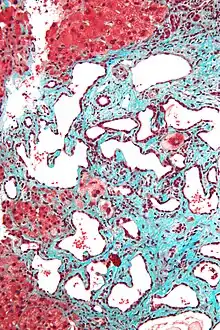

- Histopathology of a bile duct hamartoma, high magnification, H&E stain. It shows typical features of bile duct hamartoma:

- Micrograph of a bile duct hamartoma. Trichrome stain, high magnification

- Low magnification micrograph of a bile duct hamartoma. Trichrome stain.